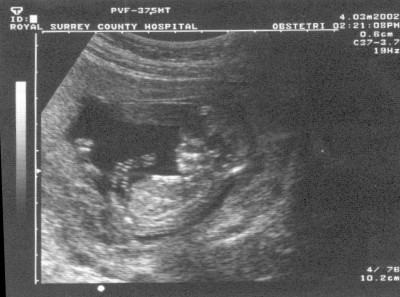

С 7 недель различают голову и тело малыша, с 8 виден позвоночник и конечности, с 11–12 недель просматриваются почки, мочевой пузырь, печень, желудок. Как правило, именно на этом сроке будущая мама делает свое первое УЗИ (врачи рекомендуют 12 недель). УЗИ первого триместра проводится трансвагинально (датчик вводится во влагалище). Ребенок уже достаточно развился, чтобы увидеть эмбрион и проверить наличие отклонений (на этом сроке еще возможно прерывание беременности). Кроме того, УЗИ, сделанное на сроке 11 – 12 недель, помогает выявить патологии матки такие как: повышенный тонус, миомы, аномалии в развитии. На двенадцатой неделе можно услышать сердцебиение крохи с помощью специального прибора - допплера. Врач также измеряет копчико-теменный размер (КТР)- 6,5-9 см, вес - 10-15г., объем околоплодной жидкости – около 50 мл. Смотрят как прикрепилась плацента. На 12-й неделе в некоторых случаях уже можно определить пол ребенка.